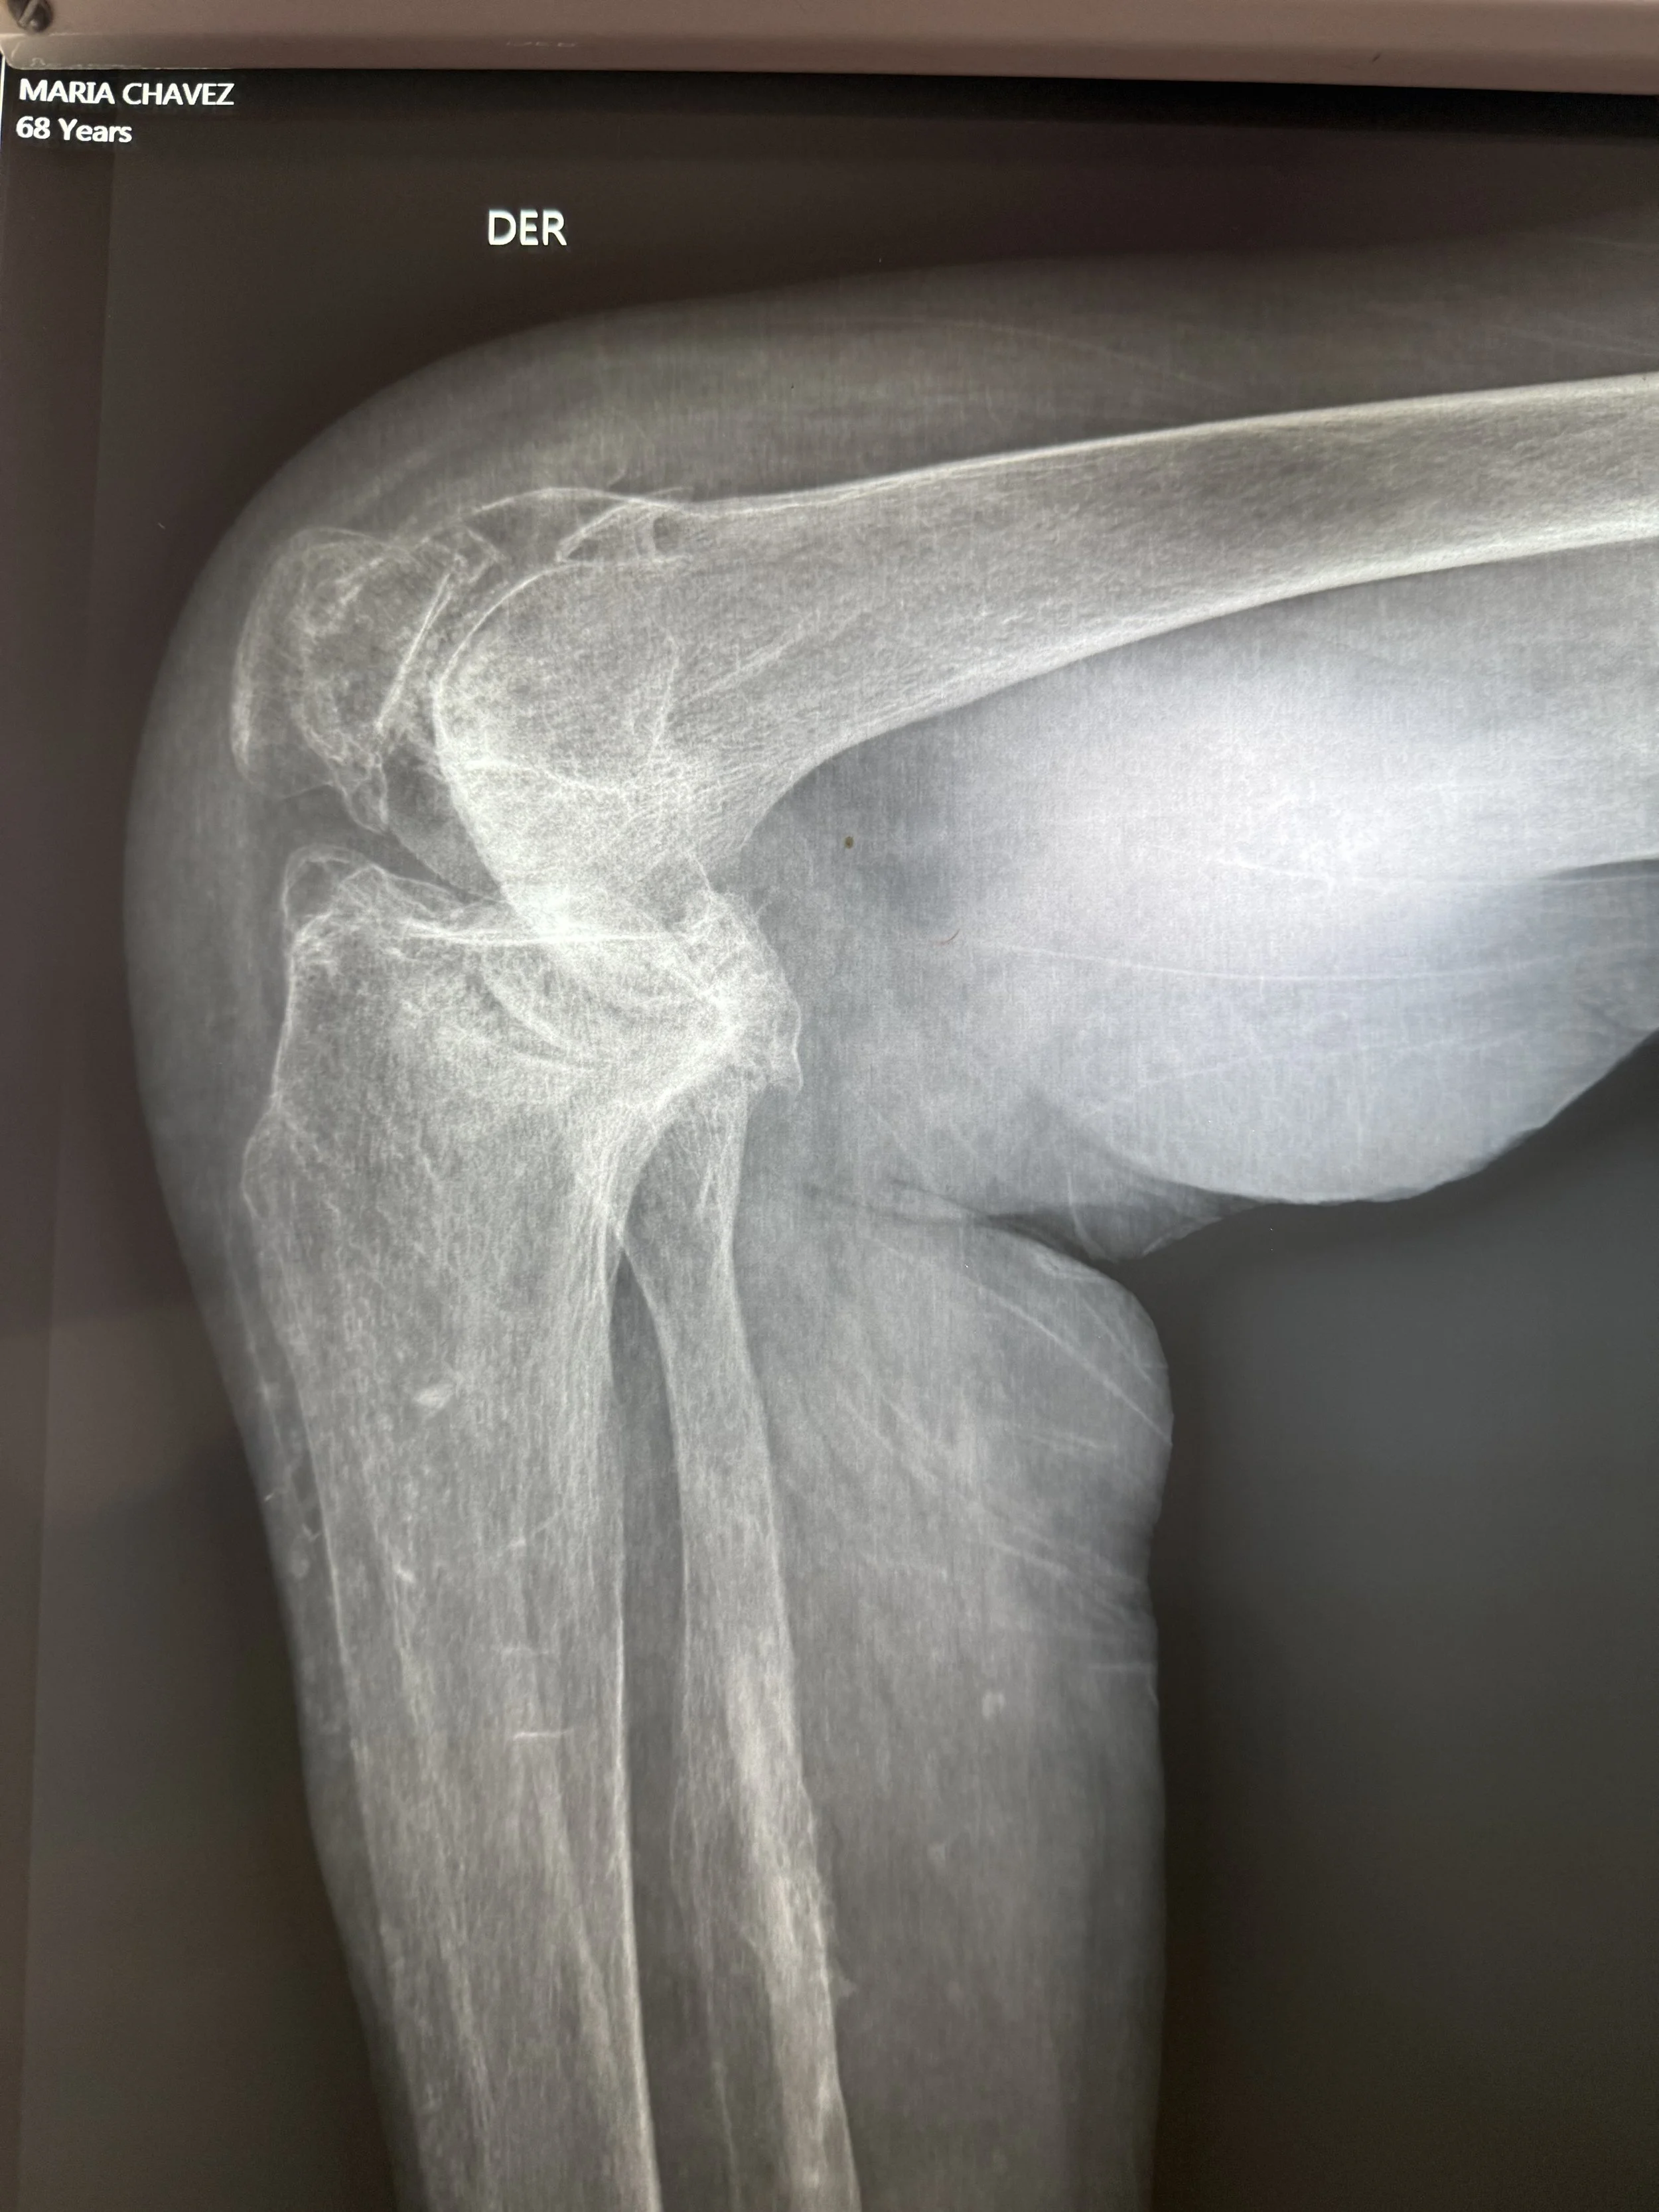

Today, we had the humble privilege of seeing over 100 patients in need of surgical care for hip, knee, foot, and ankle deformity. We will begin tomorrow with 6 operating rooms, 25 cases planned, 9 surgeons, 7 anesthesiologists, and 43 health care professionals working together.